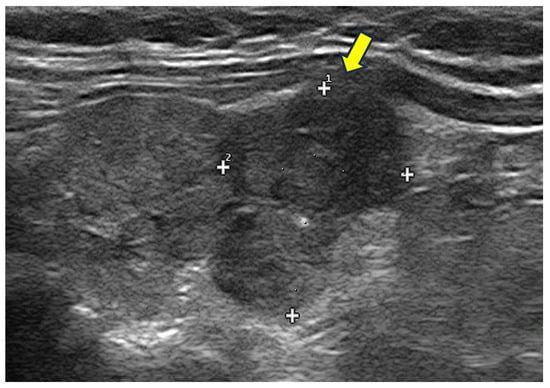

4. Thyroid Nodules

4.1. How to Assess a Clinically Relevant Thyroid Nodule: The Role of Ultrasound